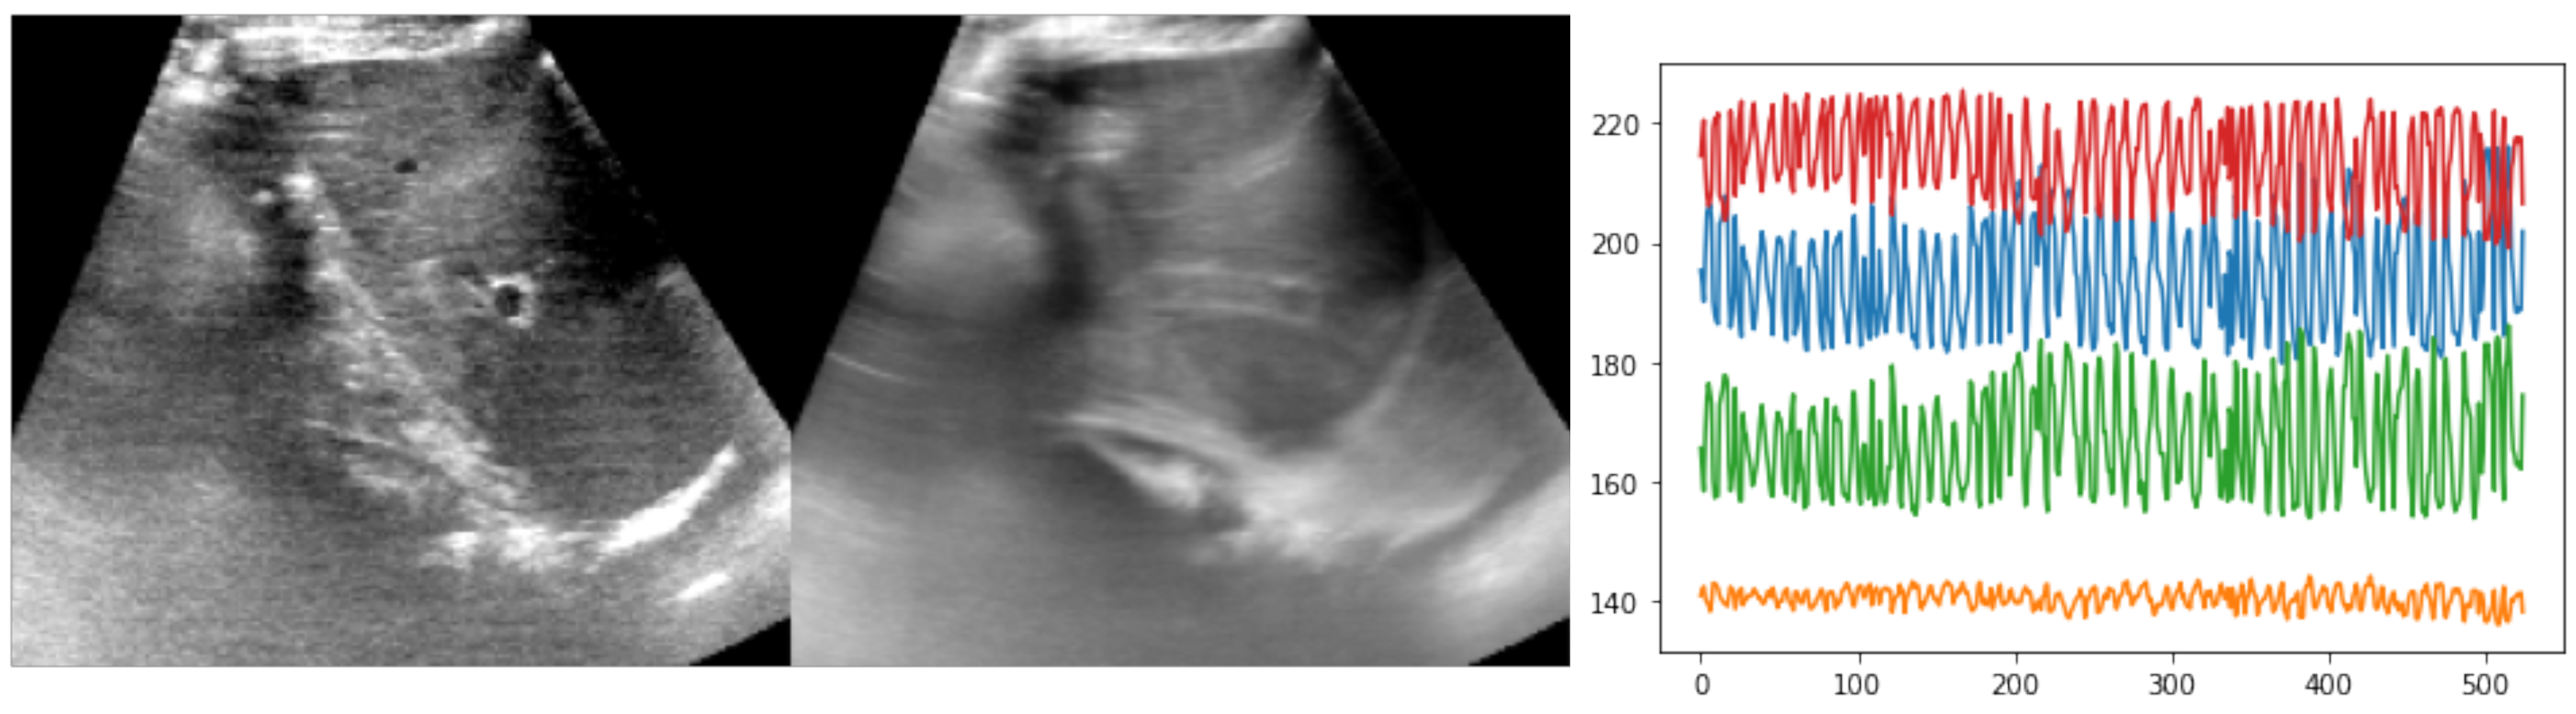

Figure 4. Example of reference frame and temporal average across one sequence from the ETHZ dataset, along with a plot of the observed motion, based on expert annotations (xy-coordinates for two landmarks). The temporal average, which showed substantial blurring of anatomies over time, as well as the large and rapid xy-coordinate changes in the annotations highlighted the difficulty of the registration task.